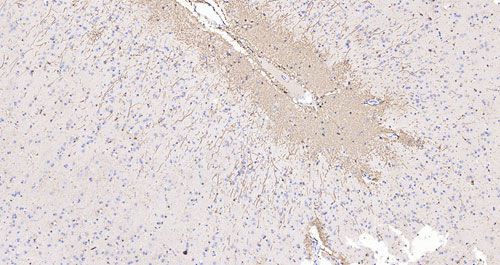

猴腦IHC-GFAP_0.2x

猴腦IHC-GFAP_10.0x

免疫組化,是應用免疫學基本原理——抗原抗體反應,即抗原與抗體特異性結合的原理,通過化學反應使標記抗體的顯色劑(熒光素、酶、金屬離子、同位素)顯色來確定組織細胞內抗原(多肽和蛋白質),對其進行定位、定性及定量的研究,稱為免疫組織化學技術(immunohistochemistry)或免疫細胞化學技術(immunocytochemistry)。傳統的石蠟切片由于玻片的限制,大組織的形態結構不能完整的呈現在鏡下,特制大玻片和全景數字掃描可以很好的解決這一難題。

切片脫蠟至水-抗原修復-3%的雙氧水處理-畫圈-血清封閉-一抗4℃過夜孵育-二抗室溫孵育-顯色-蘇木素染核-脫水、透明、封片-鏡檢